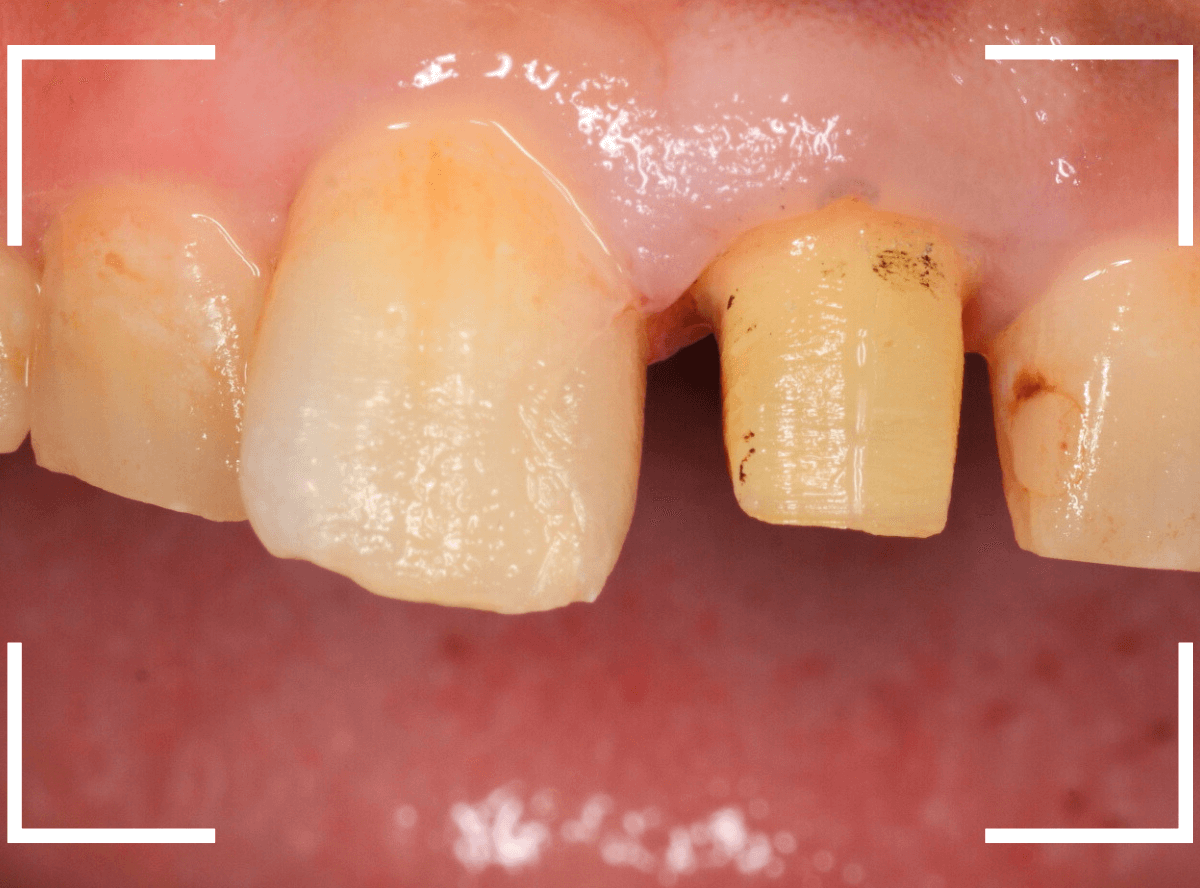

新たに、ファイバー・コアを製作し、setします。

今回は、オール・ジルコニアでの治療を希望されましたので、最終の型を取ります。